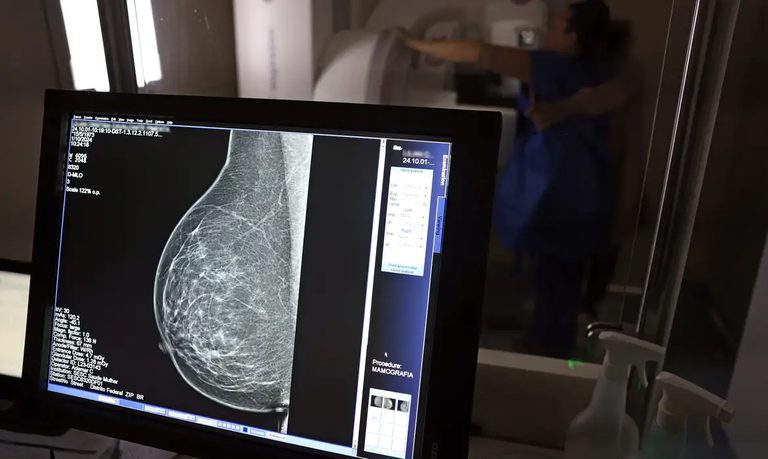

Norma publicada nesta sexta-feira (19) no Diário Oficial da União determina que o exame será garantido a todas as mulheres a partir dos 40 anos, conforme diretrizes do Ministério da Saúde, que poderão estender o procedimento a outras faixas etárias

Foi publicada no Diário Oficial da União desta sexta-feira, 19 de dezembro, a Lei nº 15.284 , que fortalece o acesso das mulheres ao exame de mamografia fornecido pelo Sistema Único de Saúde (SUS). A partir de agora, o procedimento é garantido a mulheres a partir dos 40 anos de idade. Anteriormente, a idade em que o atendimento era oferecido, salvo casos especiais, era 50 anos.

A garantia ao exame se dará mesmo que as mulheres não apresentem sinais ou sintomas de câncer. A faixa etária dos 40 aos 49 anos concentra 23% dos casos da doença e a detecção precoce aumenta as chances de cura.

AMPLA COBERTURA — Em 2024, o Sistema Único de Saúde (SUS) realizou aproximadamente 4 milhões de mamografias para rastreamento e 376,7 mil exames diagnósticos. Esses números refletem a manutenção de uma ampla cobertura no país, reforçando a importância do rastreamento e do diagnóstico precoce para salvar vidas e garantir mais qualidade na atenção à saúde das mulheres.